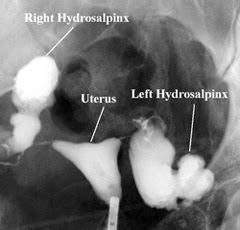

In a woman with hydrosalpinx, the fallopian tubes look like sausages, like the picture below.

![]() |

| Woman with Hydrosalpinx |